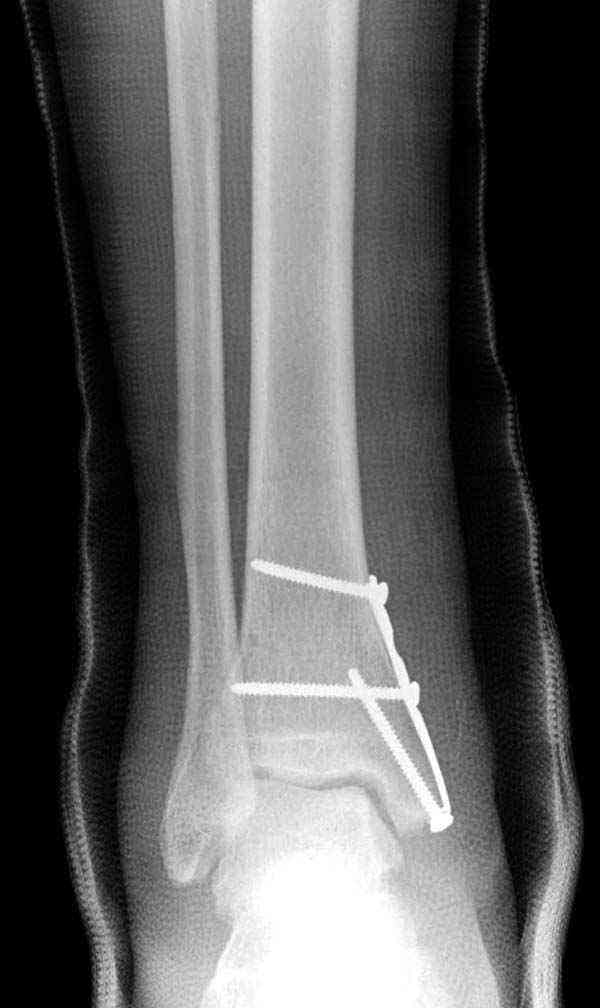

Случай прошлого года:пациентка-молодая ,крупная женщина ,30лет.Травма в начале апреля 2009г-пронационный перелом лодыжек с подвывихом стопы.Ко мне обратилась через 35 дней,прооперирована 22.05.2009г.Внутренняя лодыжка фиксирована по Веберу,наружная реконструктивной пластиной с наложением болта-стяжки.Иммобилизация "сапожок" в течении месяца,затем пригипсовано "стремя".Гипс снят 10.07.2009г

Достаточно быстрое восстановление функции.В октябре 2009г-почувствовала боль,в области рубца над гайкой открылся свищ.На Р-граммах-консолидация переломов и смещение гайки по стяжке.10.11.2009г-конструкции удалены,санация,заживление ран.В настоящее время пациентку ничего не беспокоит.На операции-раскручивание гайки-болталась на конце стяжки.Вопросы:какой механизм раскручивания и что я неправильно сделал?Свои версии:1)в области синдесмоза успела образоваться рубцовая ткань,которая при движении в суставе"пружинила",поскольку голеностопный сустав является спиральным, то и биомеханика подобна кривошипному механизму.2)Реконструктивная пластина не "реконструировалась" по форме лодыжки.Наложил,как есть.То есть подпружинивала сама пластина.Ну,это мои догадки.Что нужно,чтобы избегать впредь таких,пусть и не "страшных"осложнений:Рассверливать через лодыжку область синдесмоза?Ставить шайбу-гровер?Тщательно моделировать пластину?Прилагаю сравнительные снимки-сразу после операции и перед удалением конструкции.

Визуально никаких вопросов по репозиции не было.Да и на основании чего сомнения,что наружная лодыжка не полностью репонирована или прорезалась проволка ???Я не вижу...Снимок после репозиции справа.

Раз ,есть желание посмотреть другую проекцию выкладываю-ну лучшего качества нет...